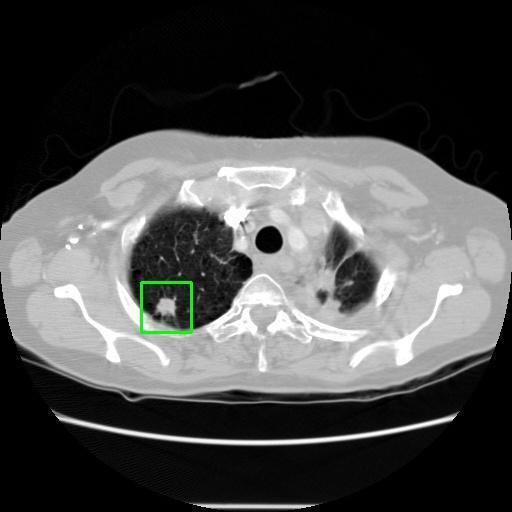

We developed an AI-based system using deep learning models for analyzing lung CT scans to detect and classify pulmonary nodules. We chose the YOLOv11 architecture for its enhanced object detection capability and adapted it specifically for medical imaging, incorporating pixel-level precision and severity classification.

Classification into three severity levels with colored bounding boxes.

Successfully built and deployed an AI model (YOLOv11) capable of detecting lung nodules in CT scans with high accuracy and real-time performance.

Designed a severity classification system that categorizes nodules into null, moderate, and severe using colored bounding boxes, assisting in rapid clinical decision-making.